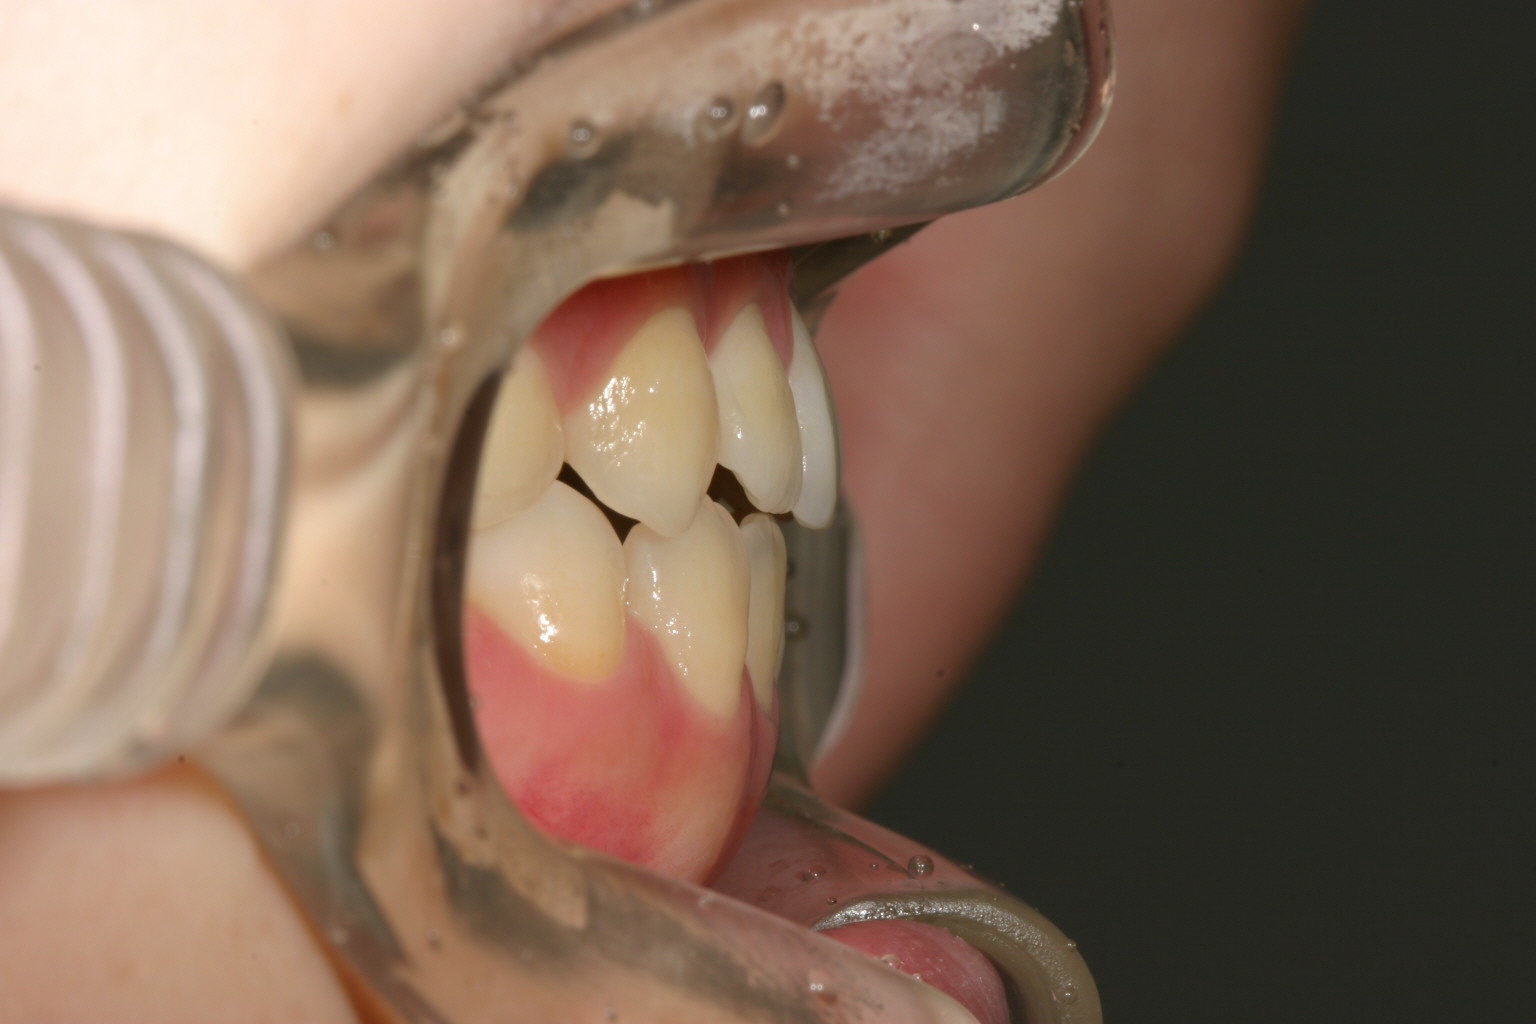

側面観も叢生の為出っ張ってます。

開咬も改善し最高のオーバージェットです。

全体的にアーチが尖ったV字歯列をされてましたのでU字に改善させ、また臼歯部を圧下させる方法により前歯を咬合させました。

そのまま前歯を引っ張ったんじゃ後戻りを生じさせる可能性があるからです。